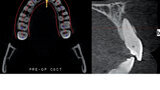

Navigovaný endodontický přístup u kalcifikovaných frontálních zubů: Kazuistika